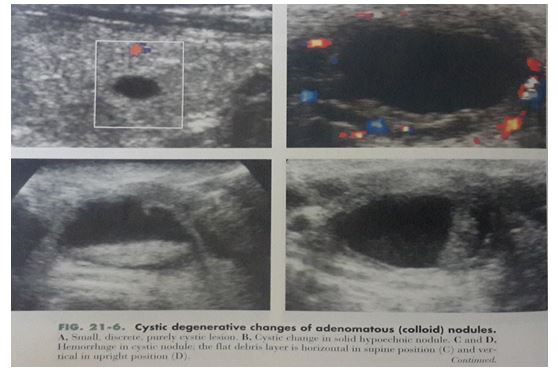

– Thay đổi hình ảnh siêu âm bướu giáp là do thoái hóa (Hình 4)

+ Thấy 1 vùng trống âm: Là do thanh dịch hay dịch keo.

+ Có cấu trúc echo trong dịch hay mức dịch – dịch là do xuất huyết.

+ Thấy chấm sáng với vệt mờ ở đuôi là do tỷ trọng của các chất keo.

+ Bên trong có thể tháy các vách mỏng, trên doppler có tín hiệu mạch trong các vách (Có thể nhầm với ung thư tuyến giáp dạng nang nhú hiếm gặp)

Hình 4: Nốt thoái hóa dạng nang tuyến (Nang keo)